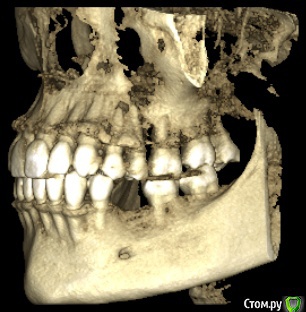

marilinka Опубликовано 28 февраля, 2016 Поделиться Опубликовано 28 февраля, 2016 Уважаемые доктора! Дело в том, что 1 марта у меня назначена имплантация нижних 5, которых никогда не было, первичная адентия. Верхняя 5 с одной стороны сильно опустилась, ортопед предложил, убрать ее под коронку, предварительно обточив, чтобы хватило места для коронки. И все бы ни чего,если бы буквально в течение недели ситуация во рту не поменялась бы, передние зубы стали упираться в друг друга, не сильно и не всегда, как зубки "поставишь", есть ощущение, что на снимках норм прикус, а сейчас занижен. Присутствуют болевые ощущения в скулах и висках, щеки пропали и самое страшное появилась носогубка. Доктор по поводу этого говорит, что протезируемся именно для этого, чтобы разгрузить сустав. В чем собственно мой вопрос хватит ли места для нижней пятерки, с той стороны где нет 2 зубов? Есть ли занижение прикуса и как с этим быть если есть? Не усугубит ли имплантация состояние внчс? Может стоит сделать новый снимок, слепки, которые кстати не делали и отложить пока имплантацию, раз у меня есть ощущение изменений во рту? С доктором общалась только по телефону, когда начало это беспокоить, раньше 1числа в больницу не попаду, нахожусь в 200 км от нее. Доктору доверяю, про таких как он говорят золотые руки, в паре с ним ортопед кмн. Что смогла то прикрепила. Ссылка на комментарий

marilinka Опубликовано 28 февраля, 2016 Автор Поделиться Опубликовано 28 февраля, 2016 (изменено) http://s017.radikal.ru/i416/1602/ea/fce843bb39a7t.jpghttp://s019.radikal.ru/i631/1602/80/8cf8f17bcc98t.jpghttp://s017.radikal.ru/i431/1602/78/b66e5d9610f7t.jpghttp://s019.radikal.ru/i616/1602/61/7ccb6dbbeb23t.jpg Изменено 28 февраля, 2016 пользователем marilinka Ссылка на комментарий

marilinka Опубликовано 28 февраля, 2016 Автор Поделиться Опубликовано 28 февраля, 2016 Ну вот как то вот так зубки во рту находятся. Ссылка на комментарий

Lolopop Опубликовано 28 февраля, 2016 Поделиться Опубликовано 28 февраля, 2016 добрый вечер, места для пятерки хватит, действительно-имеется небольшой наклон следующего зуба в сторону отсутсвующего, имплантация на состояние внчс не повлияет, делайте смело Ссылка на комментарий